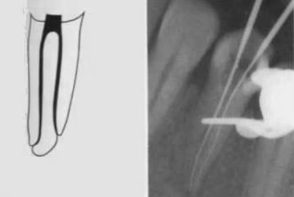

Type 4

(1-2)

one canal leaving the pulp chamber but dividing short of the apex into two separate canals with separate apical foramina